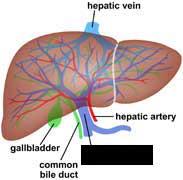

(Common) Hepatic Duct

Common bile duct

Common hepatic artery

Cystic duct

Gall bladder

Hepatic portal vein

Liver